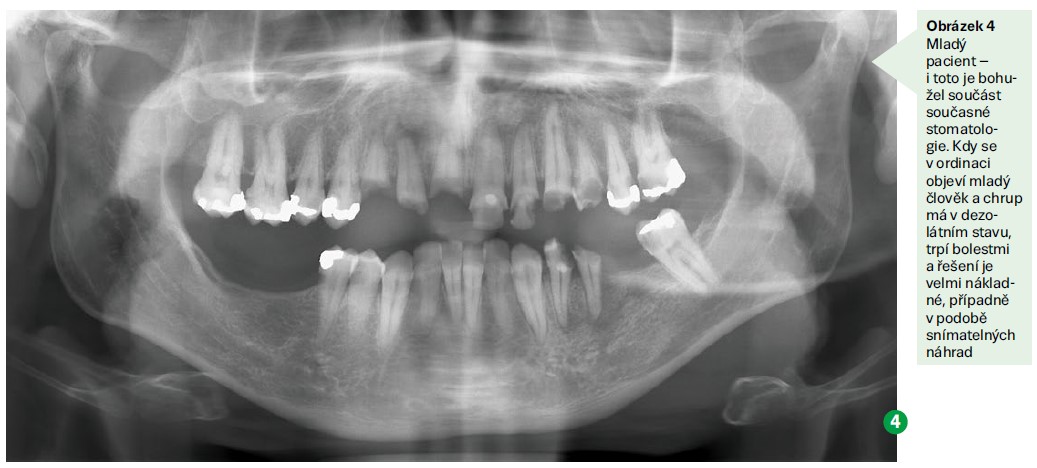

Další oblastí, kam stomatologie směřuje, je estetika. Neustále se posunují a zlepšují materiály, které se v ordinacích používají. Například materiál MTA (mineral trioxide aggregate), který se používá při ošetřování kořenových částí zubů, napomáhá hojení v jejich okolí takovým způsobem, že je dnes možné zachránit mnohem větší procento zubů než před několika málo lety.

Pokud pacientovi již zuby chybí, jsou dnes nejčastější volbou implantáty. I ty mají několik základních předpokladů pro zavedení do úst – a to dobrá ústní hygiena a dostatek kosti. Tím se vracíme k začátku článku, kdy implantát je náročnější a nesnese takovou bakteriální zátěž jako vlastní zub. V důsledku parodontitidy a nedostatečné ústní hygieny může potom mít chrup nedostatek kosti pro zavedení implantátu. Pokud pacient chrup čistí, lze nahradit kost umělými preparáty.

Výše jsou uvedeny velmi komplikované postupy, které nastávají při úrazech nebo u velmi zanedbané péče. Nejlepší formou péče o chrup je prevence, ideálně vedená už od raného dětství, díky níž se může člověk vyhnout mnoha útrapám se zuby. Je také finančně nejméně nákladná. Pokud člověk nemá kazy nebo se odstraní už jako malé, je to nejlepší stav pro všechny.